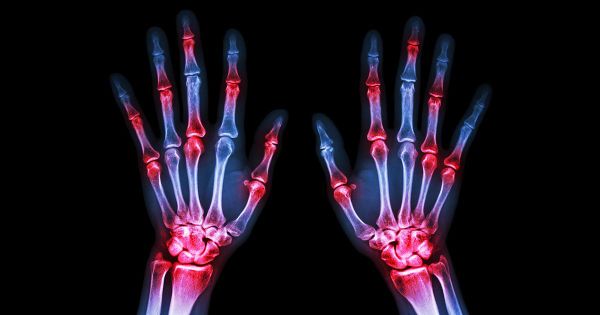

관절염을 어떻게 관리할 수 있습니까? 건강한 관절은 유연성을 유지하고 신체적으로 활동적인 상태를 유지하는 데 중요합니다. 관절염으로 고생하고 관절 통증을 자주 경험하고 있다면, 이러한 전략이 도움이 될 수 있습니다.